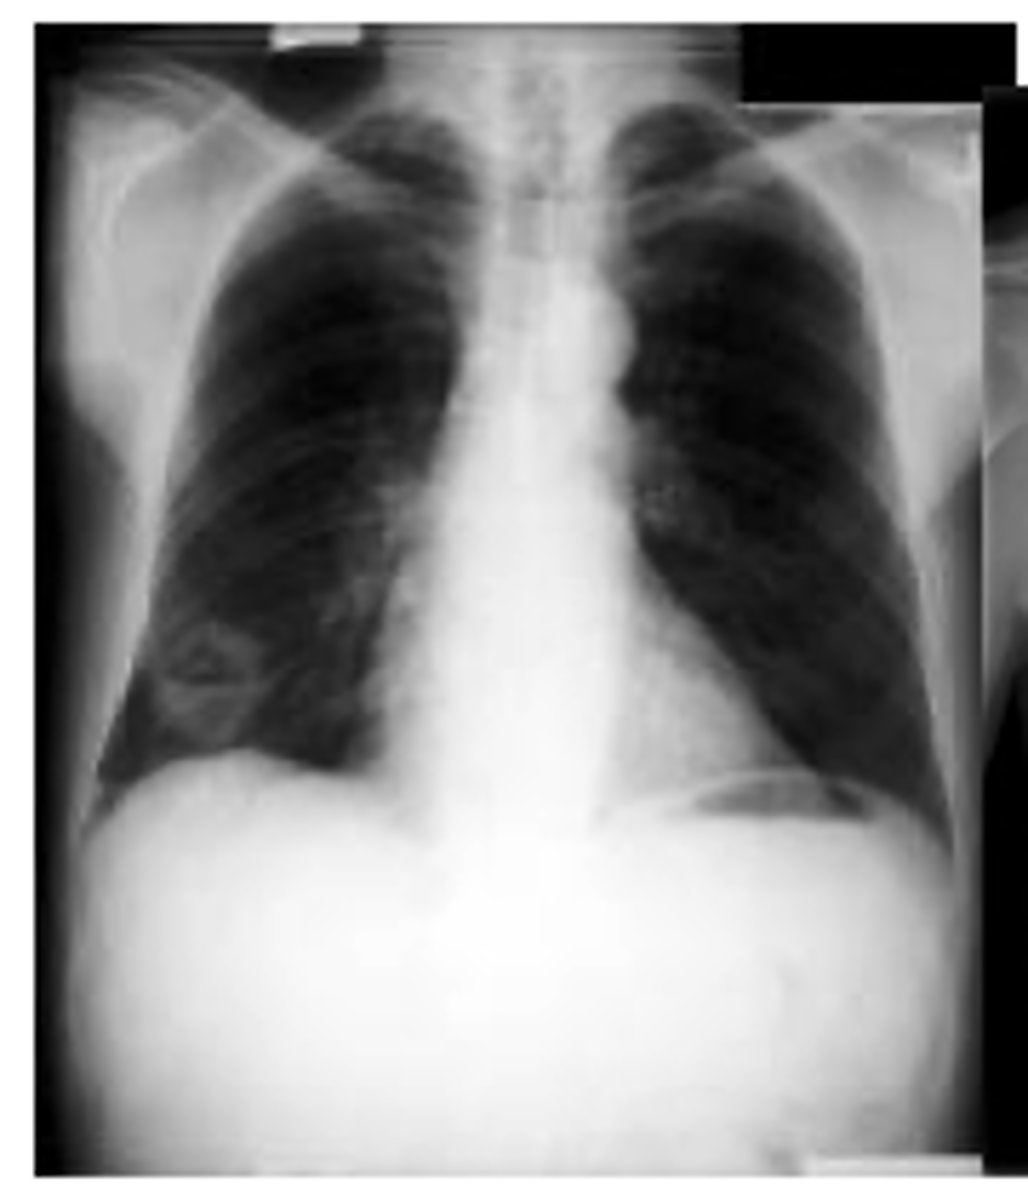

Define interstitial

tissue outside of the alveoli are affected. (diffuse)

Define alveolar

o alveolar spaces are filled with some material such as blood, pus, fluid or cells (tends to be localized)

Dx middle

lung fibrosis

What do interstitial infiltrates look like and what are some causes? IS this sign specific or non specific?

caused by acute and chronic disease processes that affect the tissue outside of the alveoli.

Interstitial processes are usually diffuse & are seen as thin white lines. May appear honeycombed (reticular)

Interstitial infiltrates are nonspecific as they can be caused by many processes such as CHF, pulmonary fibrosis, collagen vascular diseases, etc.